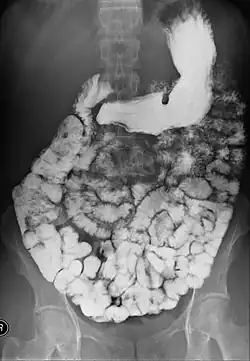

Barium is administered orally, sometimes mixed with diatrizoic acid (gastrografin) to reduce transit time in the bowel. Intravenous metoclopramide is sometimes also added to the mixture to enhance gastric emptying.[17] 600 ml of 0.5% methylcellulose can be given orally, after barium meal is given, to improve the images of small bowel follow-through by reducing the time taken for barium to pass through the small intestines, and increase the transparency of the contrast-filled small bowels.[18] Other methods to reduce transit time are to add ice cold normal saline after the administration of barium saline mixture[19] or to give a dry meal.[20]

X-ray images are then taken in a supine position at intervals of 20–30 minutes. Real-time fluoroscopy is used to assess bowel motility. The radiologist may press or palpate the abdomen during images to separate intestinal loops. The total time necessary for the test depends on the speed of bowel motility or transit time and may vary between 1 and 3 hours.[17]

- Barium follow-through examinations are the most commonly used imaging technique in assessing patients with Crohn's disease, although CT and magnetic resonance imaging are widely accepted as being superior.[1] However Barium examinations remain superior in the depiction of mucosal abnormalities.[24] The features of Crohn's disease are well described by barium follow-through examinations, appearing as a typical "cobblestone pattern", but no information is obtained regarding extraluminal disease.[28] Radiographic imaging in Crohn's disease provides clinicians with objective evaluations of small bowel regions that are not accessible to standard endoscopic techniques.[29] Because of its length and complex loops, the small intestine is the most difficult part of the gastrointestinal tract to evaluate. Most endoscopic techniques are limited to the examination of proximal or distal segments, hence Barium follow-through remains in most centres the test of choice for the investigation of abdominal pain, diarrhoea and in particular diseases manifesting mucosal abnormalities such as coeliac and Crohn's disease.[26]